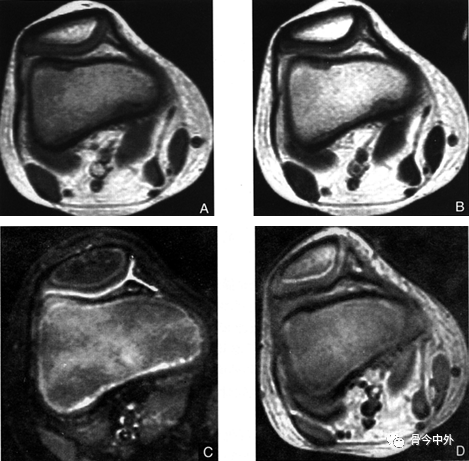

髌骨软化的磁共振表现

图片尺寸1984x1488